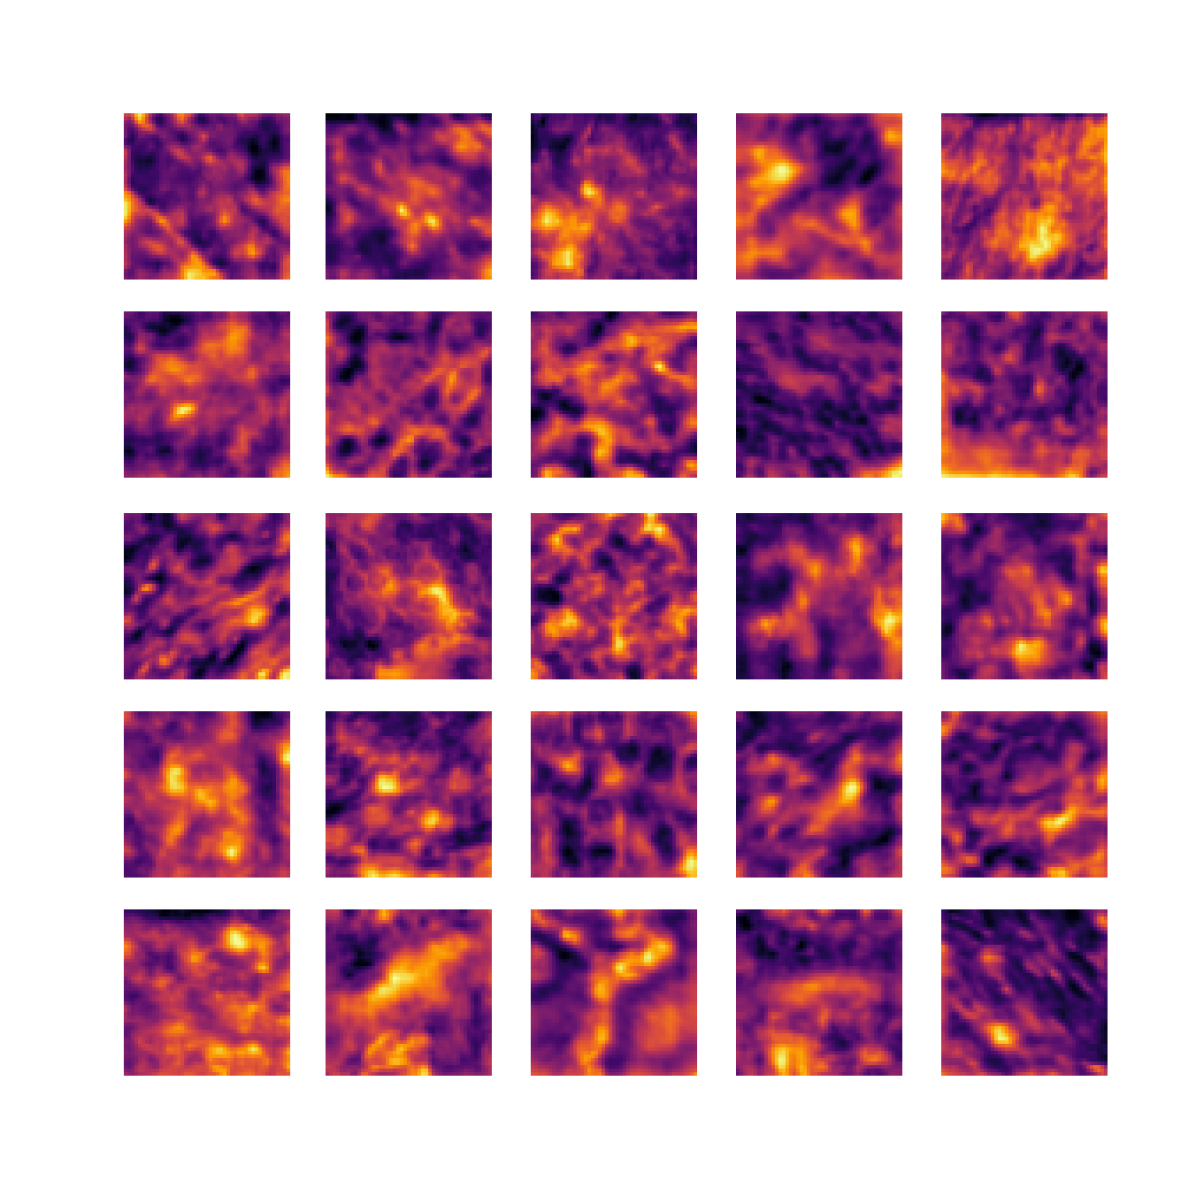

We also analyse the activation maps for each model using GradCAM as described in section S3. This offers more insight into the areas of the image which are contributing most heavily to the models’ representations. In Figure 4(b) we present some representative examples, however, a larger selection which was chosen at random is presented in Figures S10 to S25. The larger selection makes it easier to see the emergent patterns, including that privileged Siamese models tend to mainly identify features which are strongly present in both inputs, while unprivileged Siamese models tend to learn more diffuse features that are not specific to one cell phenotype or image region. TriDeNT ♆ incorporates both sets of features, learning both features specific to the privileged data and more the general features associated with unprivileged Siamese networks.

We can see in Figure 4(b) panel A that for ERG, the privileged Siamese model focuses almost exclusively on any nuclei which could be endothelial cells. As there are very few endothelial cells in the dataset, it could be an effective strategy to identify anything that could potentially be an endothelial cell to minimise the difference between the representations of the H&E model and the IF mask model. In the corresponding unprivileged Siamese image, we see that the model identifies some of these nuclei, albeit less strongly, but also focuses heavily on the other tissue and even the background, while strongly fixating on two spots of debris in the center of the image. This model has less ‘incentive’ to learn the weak features related to endothelial cells as these occur rarely and are not easy to detect, while more generic strong features such as the presence of connective tissue and the prevalence of background are more common and predictable from augmented images. We see that TriDeNT ♆ combines these two feature sets, strongly identifying nuclei while also identifying the connective tissue.

In panel C we see a similar pattern, with the privileged Siamese model fixating solely on the nuclei, while the TriDeNT ♆ model takes a more balanced approach. The unprivileged Siamese model appears to focus on a single cluster of nuclei while neglecting others, and similarly identifies an area of fibroblasts with its distinctive pattern but does not others.

In contrast to panels A and C which represent models with poor privileged Siamese results, panels B and D represent models whose privileged Siamese results were comparable to both TriDeNT ♆ and even the supervised baseline. It is therefore interesting to note that there are far more similarities between the privileged Siamese and TriDeNT ♆ models in both cases. Particularly in panel B, TriDeNT ♆ and the privileged Siamese model return virtually identical heatmaps, with both strongly identifying epithelial nuclei and neglecting the same areas of connective tissue. The unprivileged model in this case appears to focus solely on the centre of the image, giving a significantly different heatmap to the other panels.

Panel D again shows the previous pattern, with the privileged Siamese model identifying the features strongly present in the privileged data – fibroblasts – while neglecting the nuclei present. TriDeNT ♆ also strongly identifies the connective tissue, but, unlike the privileged Siamese model, does not completely neglect the nuclei. The unprivileged Siamese model primarily identifies background, and does not appear to identify the nuclei in this example.